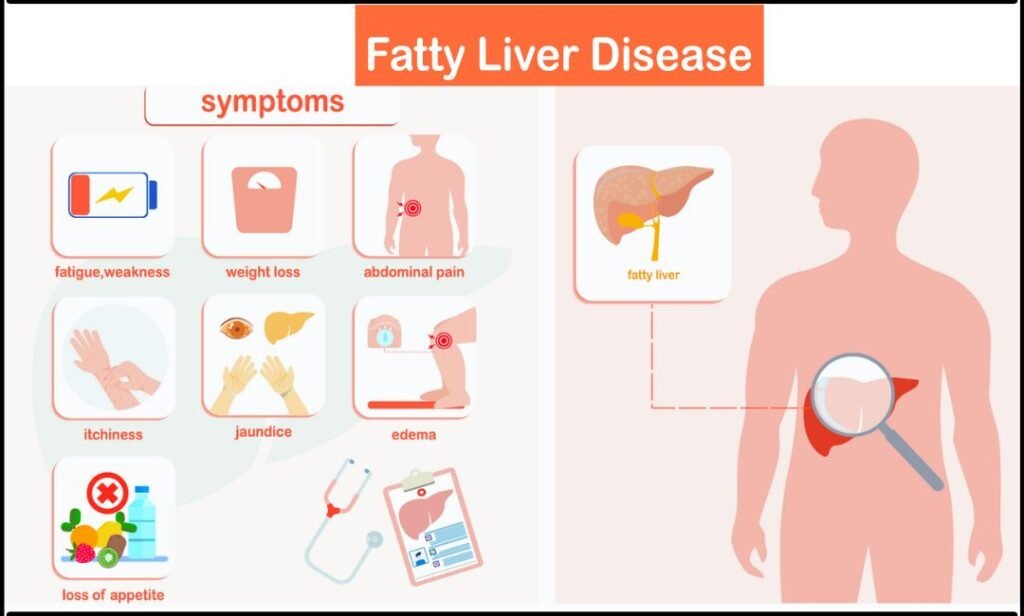

Symptoms of Fatty Liver Disease

Many patients do not feel symptoms in early stages. However, as the condition progresses, some signs may appear:

- Mild pain in the upper right abdomen

- Fatigue

- Weakness

- Loss of appetite

Sometimes fatty liver is detected during routine blood tests. Therefore, regular health check-ups are helpful.

If symptoms continue, consulting the best doctor for fatty liver in Bhopal ensures proper care.